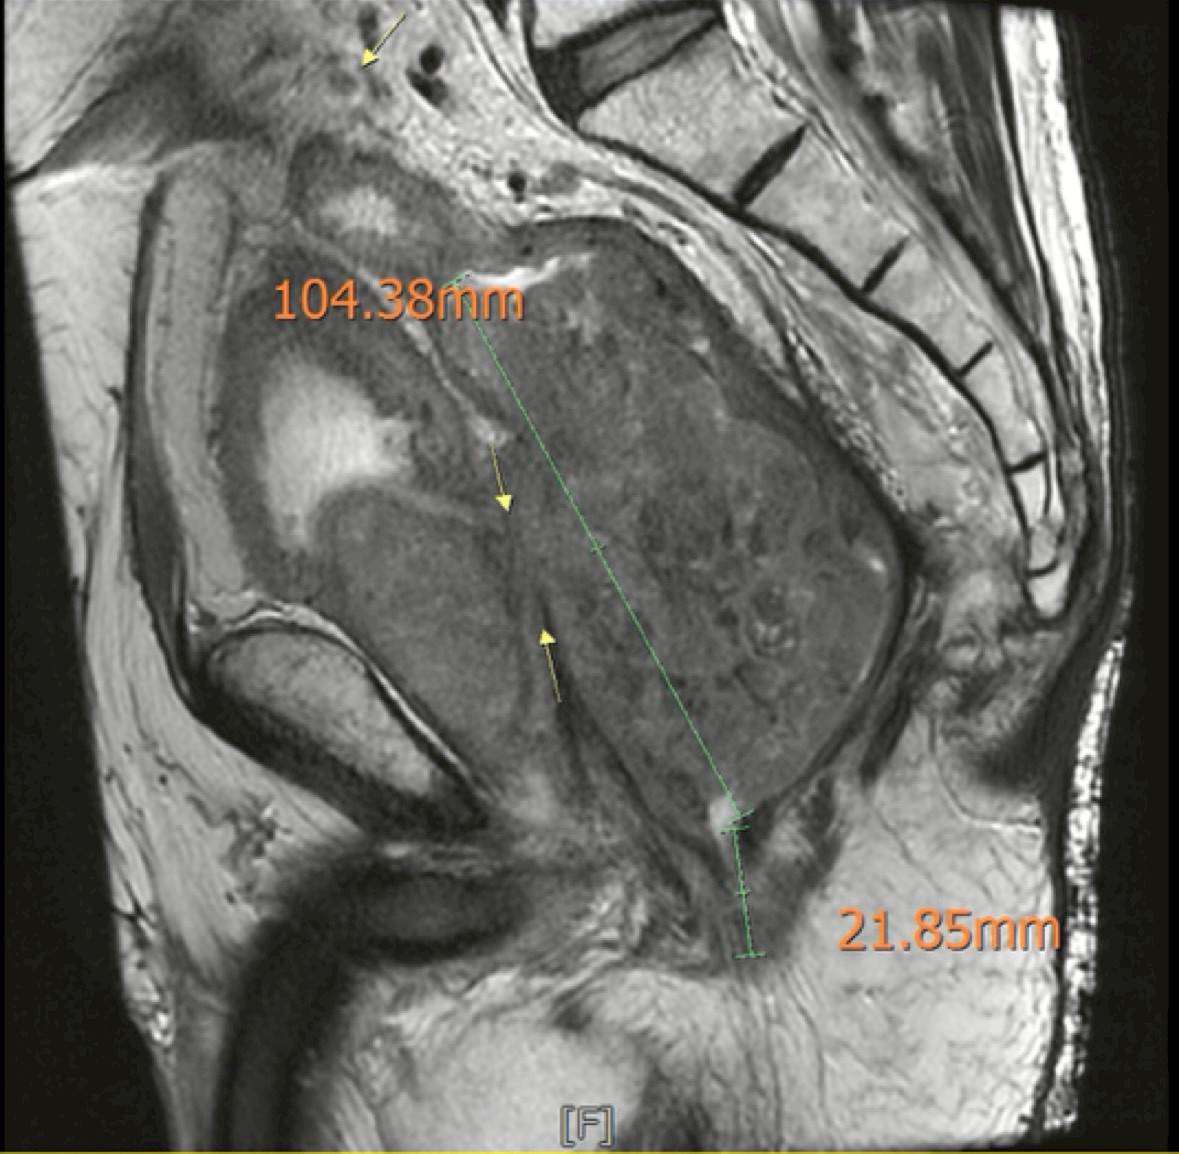

在感染穩定之後,黃晟瑋醫師重新安排影像檢查,結果顯示:腫瘤處於穩定狀態,沒有遠端轉移,也沒有明顯惡化。這代表一件很重要的事情─腫瘤仍然有機會透過手術完整切除。

中國醫藥大學附設醫院骨盆複雜腫瘤根除手術團隊(Pelvic Exenteration)安排了多團隊會議(MDT),包含外科部長柯道維、大腸直腸外科黃晟瑋醫師、泌尿科蔡禮賢醫師、整形外科黃循靜主任、放射腫瘤科簡君儒主任、腫瘤內科林哲宏醫師、影像科李哲宇醫師、復健科與營養團隊,共同討論王先生是否有機會接受骨盆複雜腫瘤根除手術(Pelvic Exenteration)。